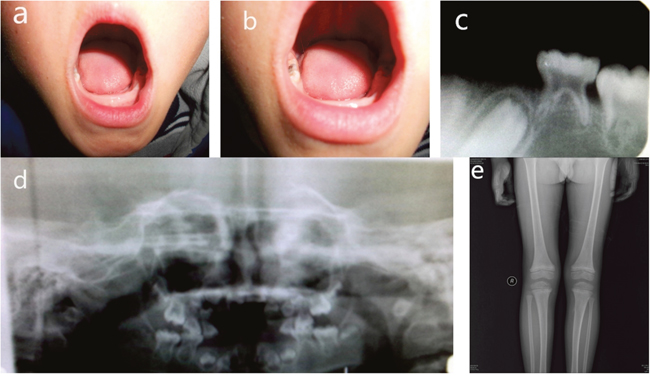

Panoramic radiographs of the proband demonstrated that the erupted teeth were normal and the radiographs of the younger brother showed reduced alveolar bone, enlarged pulp chambers, and abnormal morphology of the unerupted permanent molars. X-ray of knee joints presented metaphyseal osteoporosis changes in femurs and tibiae (Figures 2 and 3). Ultrasonographic assessment of BMD in distal radius and middle tibia showed low bone mineral density for the proband and his younger brother. In addition, their levels of serum ALP moderately decreased, whose values were 41.5 U/L and 43.4 U/L, respectively (regular scope for children 110-550 U/L). No aberrant variation in serum Ca, PTH, ESR and microelement were detected. But a high level of serum P (2.08 mmol/L and 1.97 mmol/L, respectively, normal range for children 0.90-1.34 mmol/L) and low serum 25-hydroxy vitamin D (50.40 nmol/L and 55.70 nmol/L, respectively, normal range for children 75-175mmol/L) were observed.

Figure 3: Clinical features of younger brother. (A, B) Intra-oral photograph of proband showing premature exfoliation of primary teeth. (C, D) Panoramic radiographs showing reduced alveolar bone, enlarged pulp chambers, and abnormal morphology of the unerupted permanent molars. (E) Plain films of a knee joint presenting with metaphyseal osteoporosis changes.